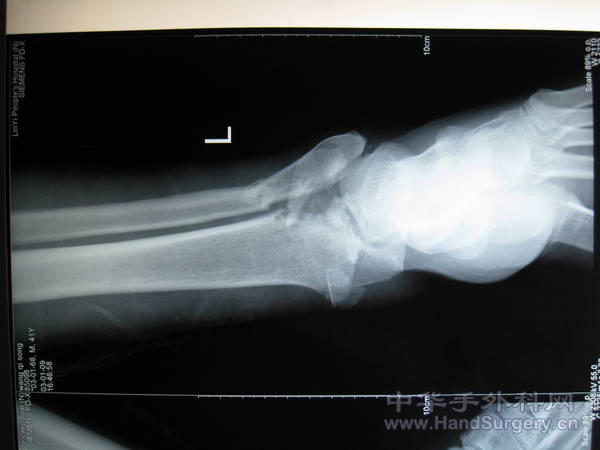

pilon骨折一例-手足外科魏宝富主任作品

这种骨折为从高坠落高能量致的损伤,损伤都较重,对重的有的主张一期行关节融合,如轻的可以行复位内固定,一般都要行植骨。

pilon骨折在哪做都是高难度手术,骨性支架的建立应该最重要,皮肤缺损对手足外科大夫来讲已经不是什么难题 ,希望看到踝关节关节面的x线或ct。

魏主任:你的手术做的很好,但是不知关节面是如何处理的,植骨了吗?是急症做的还是消肿以后做的?切口愈合如何?还有外侧的关节面好像没有处理?

对于此类骨折,手术最关键所在应该是先恢复腓骨解剖位置,其余骨折块做起来较容易些。另外需要注意植骨支撑,再者注意下胫腓关系一定要稳定!不要轻易去做融合!个人理解